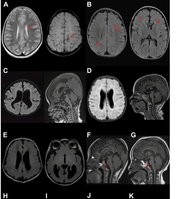

의료 영상에서 진단에 필수적인 피부 병변은 원본 그대로 보존하고, 환자의 신원만 가상의 얼굴로 효과적으로 익명화하는 AI 기술이 개발됐다. 연구팀이 개발한 이 AI는 기존 모델의 낮은 얼굴 생성 품질과 중대한 한계점이었던 인종 편향 문제를 근본적으로 해결했다. 특히 익명화된 이미지에서도 98.9%의 높은 정확도로 안면 질환을 유지해, 앞으로 어떤 인종이든 차별 없이 안전하게 의료 데이터를 활용할 수 있을 전망이다. 서울대병원 영상의학과 이동헌 교수팀(충남대 송승한 교수, 충남대 한연규 박사과정)은 인종에 따른 성능 격차를 없애고 동등한 개인정보 보호를 제공하는 안면 익명화 AI 프레임워크 ‘FairAnon’을 개발했다고 2일 밝혔다. 최근 환자 신원 보호를 위해 원래 얼굴을 가상 얼굴로 변환하는 생성형 AI 기술이 도입되고 있다. 그러나 기존 모델들이 저품질의 얼굴 이미지를 생성하는 문제와 더불어, 서양인 얼굴 데이터셋 위주로 학습된 탓에 다양한 인종 개념을 서양인 중심의 기본값과 뒤섞어 학습하는 의미론적 얽힘(Semantic entanglement) 현상이 발생했다. 이로 인해 아시아인 등 타 인종의 얼굴을 변환할 때 화질과 개인정보 보호 수준이 모두 저하